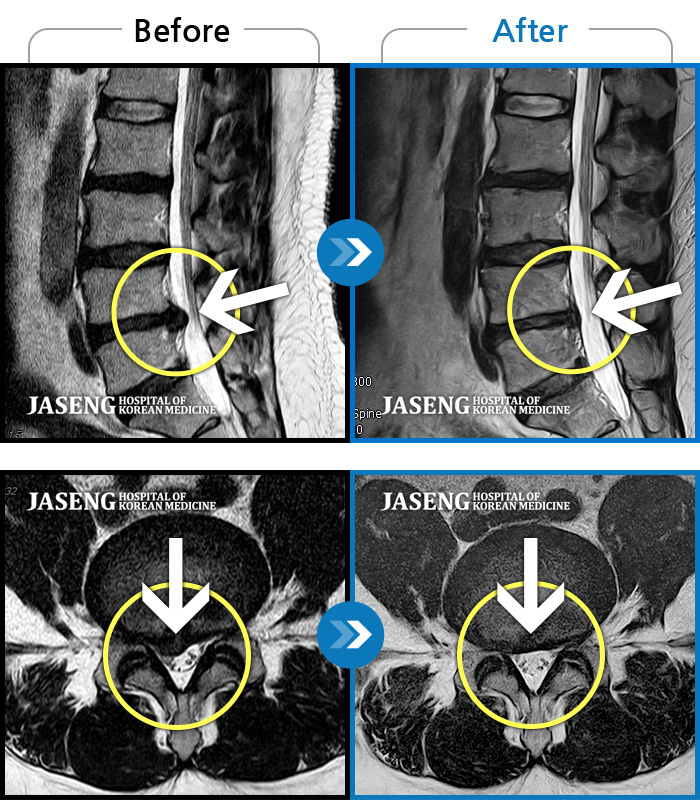

[뱸] 19.11.28~25.05.06